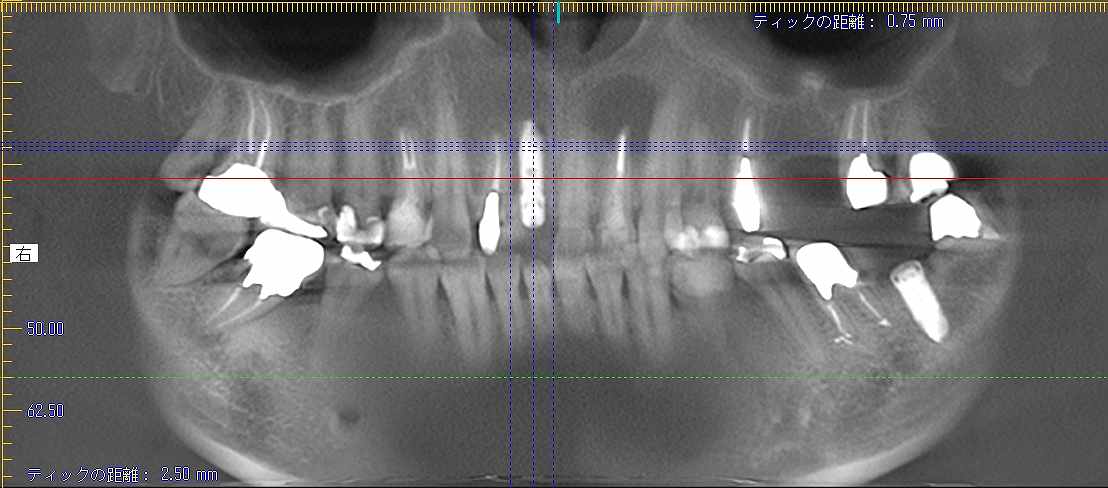

最終補綴になります

スポーツ選手なので一応、8番も残して大きく口腔内が変化しないようには配慮しています

このように入っています

臼歯部の安定を確認してから前歯部の最終補綴を行っています